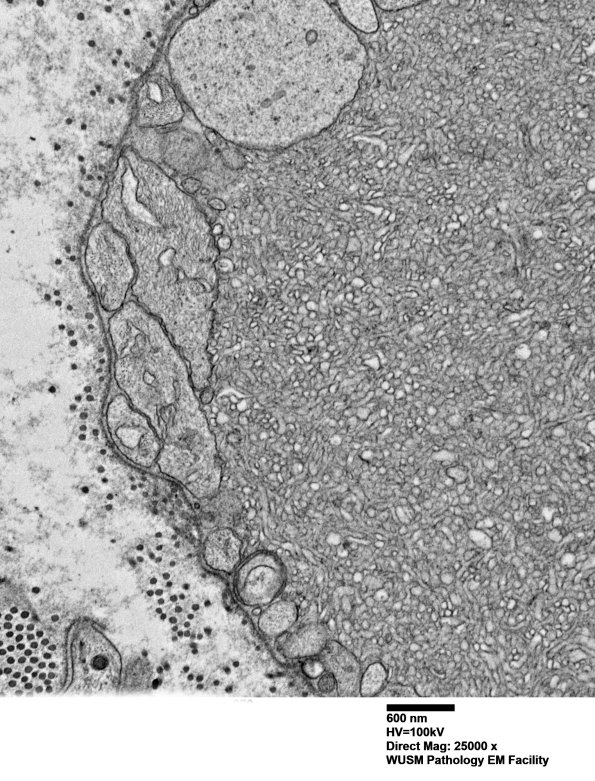

Higher magnification of image #16C9. (electron micrograph)